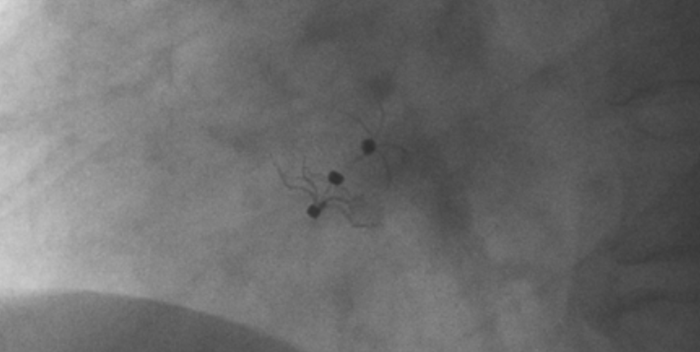

術(shù)中造影顯示患者為PFO且長隧道型,目前市場上已商業(yè)化的PFO封堵器難以滿足該患者解剖結(jié)構(gòu)封堵需求。迪創(chuàng)醫(yī)療自主研發(fā)的OmniSeal PFO封堵器自適應(yīng)性雙盤貼合設(shè)計(jì)能廣泛適應(yīng)不同PFO隧道長度的解剖結(jié)構(gòu)和形態(tài),其雙盤外包覆式阻流和隧道內(nèi)填充阻流相結(jié)合的雙重阻流設(shè)計(jì),可為此患者實(shí)現(xiàn)有效封堵。與此同時(shí),OmniSeal首創(chuàng)的完全可穿刺式設(shè)計(jì),也為此患者最大程度地保留了房間隔區(qū)域穿刺通道,以實(shí)現(xiàn)全兼容未來可能的左心系統(tǒng)二次介入術(shù)。術(shù)終造影和心臟超聲顯示封堵完全、效果良好。作為OmniSeal的首例臨床應(yīng)用,本次手術(shù)的順利完成和優(yōu)異效果充分體現(xiàn)了產(chǎn)品的設(shè)計(jì)創(chuàng)新優(yōu)勢。

影像顯示試驗(yàn)器械適應(yīng)性貼合于房間隔兩側(cè)且穩(wěn)定